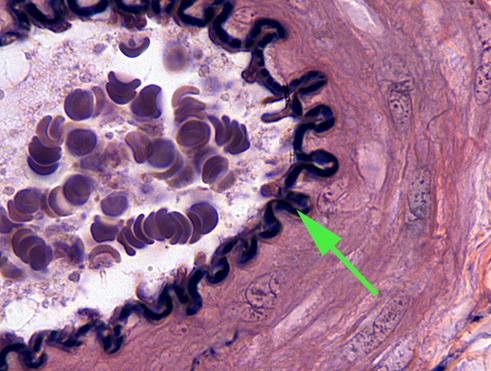

The structure labeled by the green arrows is a valve found in a lymphatic vessel.

The black twisted line is elastic tissue found in elastic arteries. The squiggly line is called the internal elastic membrane.